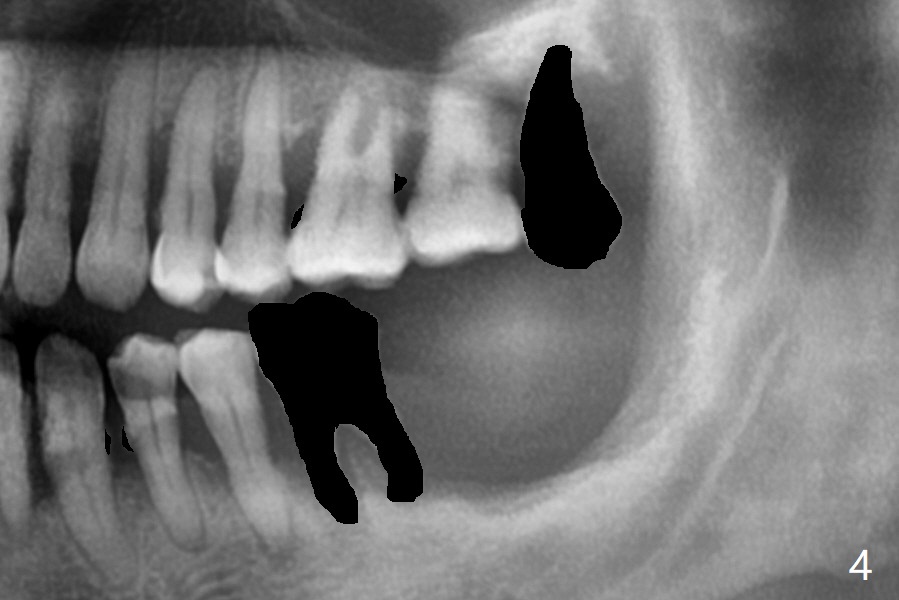

56岁男几十年拒绝牙周炎治疗,也不愿意拔除所有牙齿做全口植牙修复。17,18号牙自行脱落,现在要求拔除16,19;18,19种植(图一),后者牙龈厚(双箭头),但是18号牙骨质高度不足(图二),勉强植入5x7.3毫米植体。15,16骨质吸收严重(图三),16,19拔除,局部深洗后(图四:黑色),为了延长15号牙使用期,16号牙牙槽窝植骨(图五:红色)。19号牙种植徒手,因为邻牙(包括20,21号牙))松动,做导板不准确,钻洞使用环形钻头(图六),保留骨塞(bone plug),用于18号牙骨质高度骨块移植。19号牙拔除后,往远中18牙位做潜行分离(图七:黑色)。19种植(绿色),基台(粉红色),骨粉(圆圈),临时牙冠(白色),16号牙粘性骨粉植骨(红色),PRF,Cytoplast覆盖(白线),缝合。从19号牙钻洞取来的骨塞,塞入18号牙潜行分离处(图八);利用临时牙冠和22号牙以及钢丝,树脂固定20,21号牙(蓝色),并且降低咬合(*)。最后,用螺钉固定骨塞(图九:深蓝色)。